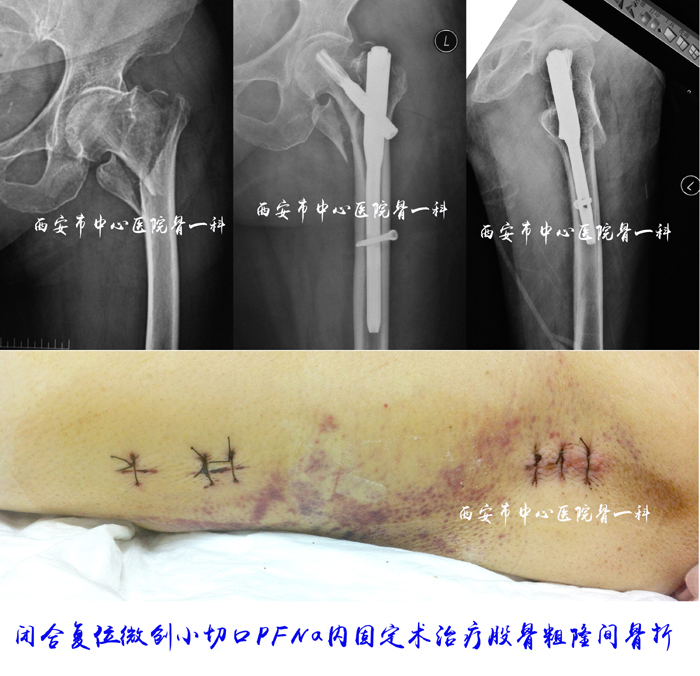

闭合复位微创小切口PFNa内固定治疗股骨粗隆间骨折1

闭合复位微创小切口PFNa内固定治疗股骨粗隆间骨折2

闭合复位微创小切口PFNa内固定治疗股骨粗隆间骨折3

闭合复位微创小切口PFNa内固定治疗股骨粗隆间骨折4